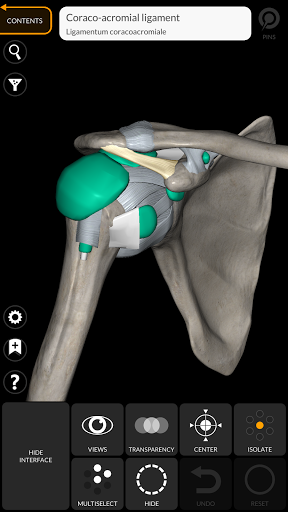

"Anatomy 3D Atlas" vous permet d'étudier l'anatomie humaine de manière simple et interactive.

Grâce à une interface simple et intuitive, il est possible d'observer chaque structure anatomique sous n'importe quel angle.

Les modèles anatomiques 3D sont particulièrement détaillés et avec des textures jusqu'à une résolution de 4k.

La subdivision par régions et les vues prédéfinies facilitent l'observation et l'étude de parties individuelles ou de groupes de systèmes et les relations entre différents organes.

• Option pour masquer ou isoler un ou plusieurs modèles sélectionnés

• En sélectionnant un modèle ou une épingle, le terme anatomique associé apparaît

Ligaments ajoutés